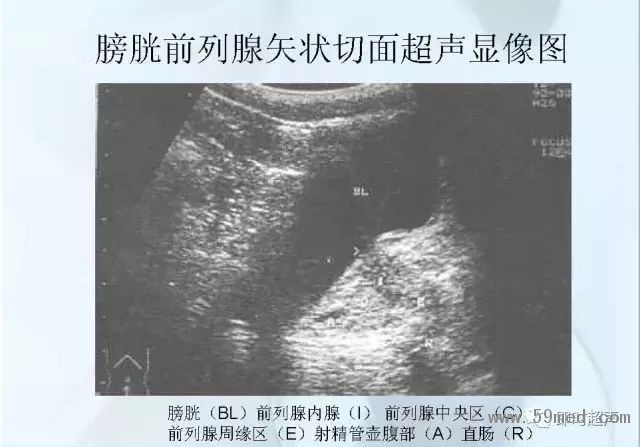

![]() ![]() ![]() ![]() ![]() ![]() ![]() ![]() ![]() ![]() ![]() ![]() ![]() ![]() ![]() ![]() ![]() ![]() ![]() ![]() ![]() ![]() ![]() ![]() ![]() ![]() ![]() ![]() ![]() ![]() ![]() ![]() ![]() ![]() ![]() ![]() ![]() 【注:本文來源于即時超聲,版權(quán)歸原作者所有,如有侵權(quán) 請聯(lián)系 速刪】 =========================== 【閱精彩*悅分享】隨手點擊轉(zhuǎn)至朋友圈,與大家一起分享精彩資訊!當(dāng)然您也可以通過以下方式找到我,與您共同分享藍(lán)韻影像超聲的更多精彩!微信號:landultrasound 電話:+86-0755-66869896 24小時客服熱線:400-888-6452